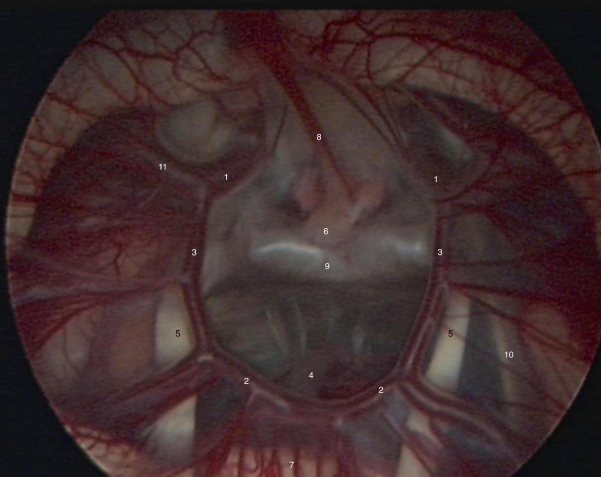

图3:内镜下的willis环

患儿,4个月大,男婴。因进行性头围增大,同时发现有脑积水而住院治疗。入院时未发现明确的病因,因此给予脑室-腹腔分流术治疗。在此后常规随访期间,患儿头围仍继续增大。13个月龄时,复查头部MRI显示颅腔内一个鞍上蛛网膜囊肿。患儿神经系统检查正常。医生再次进行内镜手术,以对囊肿及持续的脑积水进行治疗。在进行治疗的过程中,可以清楚地看到willis环,垂体柄,动眼神经和中脑等解剖结构。术后患儿恢复良好, 2天后出院回家。而在稍后的随访过程中,患儿亦未有任何其他并发症出现。